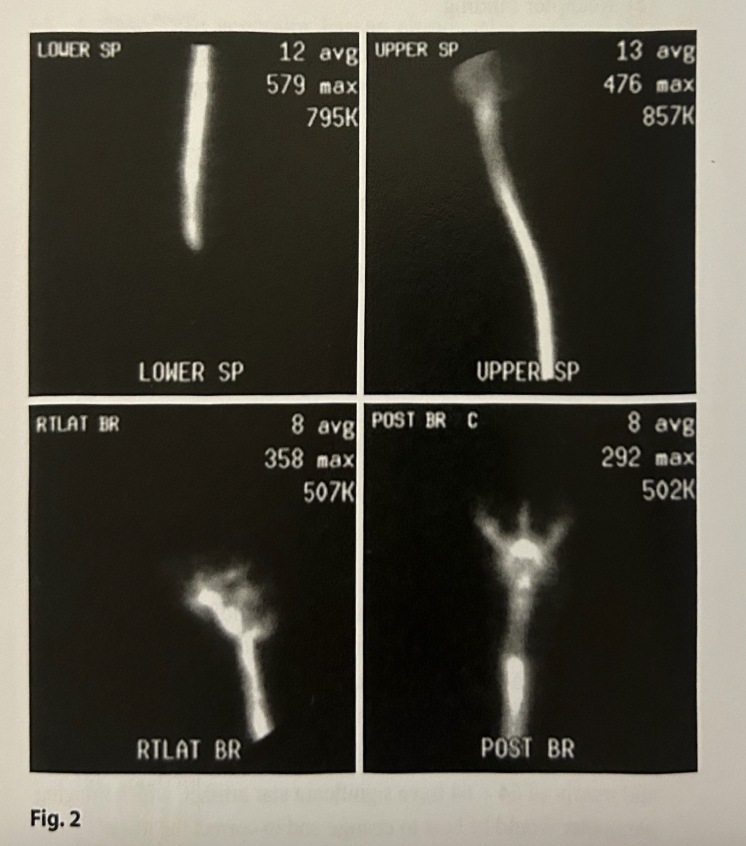

The images in Fig. 2 were taken 2h following the intrathecal injection of a radiopharmaceutical. These are images from a:

Cisternogram